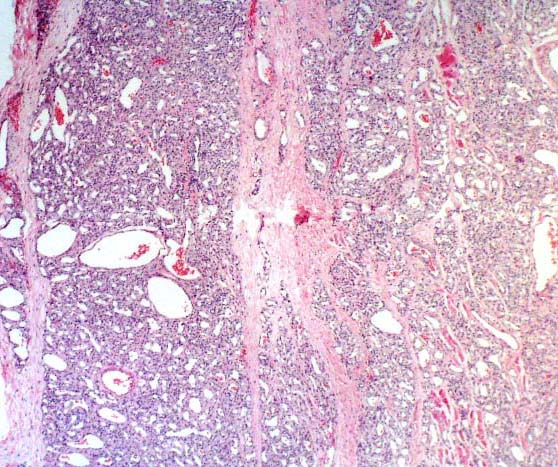

Histopathology:

Histologically angiomatosis may show two patterns.

The first and more common pattern show proliferation of

vessels of different size, composed of large venous,

cavernous, and capillary-sized vessels scattered in soft and

fat tissue.

The venous vessels are remarkable for their irregular, thick

walls that have occasional attenuations and herniations.

A rather characteristic features is the presence of small

vessels clustered around the wall of large vein.

The second pattern is identical to that of capillary

hemangiomas, exept that the nodule of tumor diffusely

infiltrate the surrounding soft tissue.

The abundance of fat within angiomatosis has given rise to

the alternative designation of "infiltrative angiolipoma".